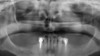

L’image radiologique post-opératoire montre les deux implants ancrés dans la poudre d’os qui a servi à combler le sinus maxillaire.

Sur ce premier cliché panoramique d’une patiente de 76 ans, il est visible que la racine de la molaire pilier du bridge est facturée. Le sinus maxillaire sus-jacent est encolbré et possiblement infecté.

A un an après l’exatraction, la pathologie sinusienne est très réduite et devenue bénigne.

A trois ans, l’aspect du comblement sinusien est satisfaisant et la patiente profite chaque jour de l’absence de toute prothèse amovible dans sa bouche. La patiente est disciplinée quant à l’utilisation de ses brossettes.